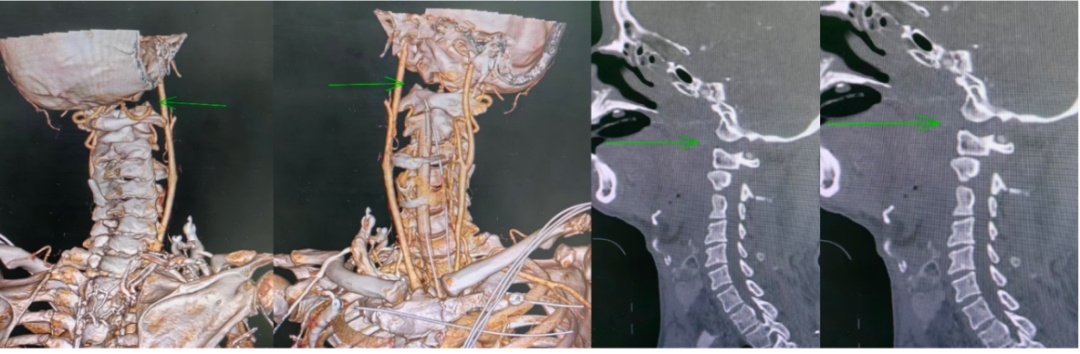

▲寰枕关节脱位(“头颈分离”)

影像检查结果清晰地显示

连接头颅与第一颈椎(寰椎)的关节

完全脱位

同时伴有颅内出血

这里是生命的“中枢开关”

——延髓所在

它负责调控心跳、呼吸和血压

关节脱位就像一把钳子紧夹核心神经

导致呼吸衰竭和全身瘫痪